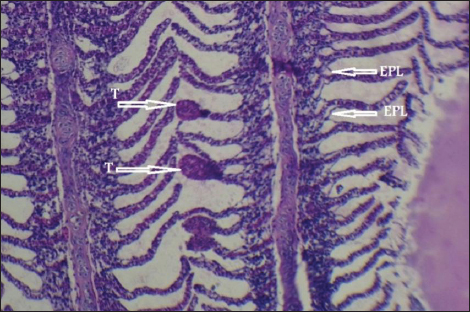

Histopathological findings of gill section showed telangictatisis and epithelial lifting in secondary lamellae (Fig. 7) with hemorrhage and blood congestion (Fig. 8), also, the result showed the central venous dilation with blood congestion and epithelium hyperplasia with complete fusion of the secondary lamellae (Figs. 9 and 10) and edema in the filamentary epithelium (Fig. 11) in addition to mononuclear cells infiltration (Figs. 12 and 13).

Fig. 9. Histopathological sections of gill of C. carpio showing central venous dilation (D) with blood congestion (BC), epithelium hyperplasia (HP) with complete fusion of the secondary lamellae (F) (H&E X40).

Fig. 10. Histopathological sections of gill of C. carpio showing complete fusion in the secondary lamellae (F) (H&E X40).